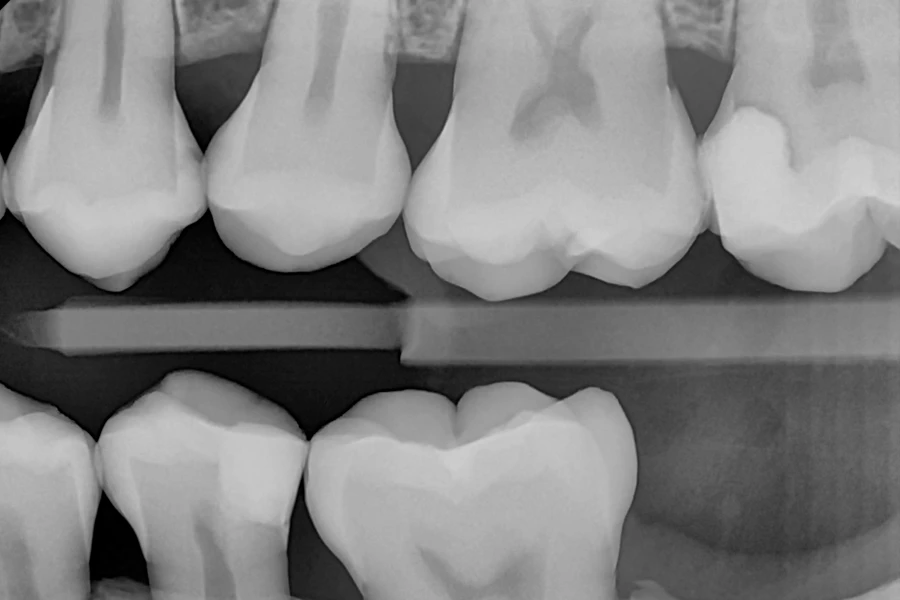

رادیوگرافی داخل دهان بایت وینگ

نوعی تصویربرداری دندانپزشکی جهت مشاهده بخشهای بین دندانی و بررسی وضعیت استخوانهای اطراف.

• بایت وینگ: برای مشاهده سطح بین دندانی و بررسی پوسیدگیهای دندانها استفاده میشود.

عکس بایت وینگ، نوعی عکس رادیولوژی دندانی است که به منظور شناسایی پوسیدگی دندان و تشخیص بیماریهای لثه ممکن است از آن استفاده شود. عکس بایت وینگ اطلاعات دقیقی درباره سطح بین دندانی و پیشگیری از بیماریهای جدی دندانی، به ویژه در نواحی غیر قابل دید برای پزشک یا بیمار، بسیار حائز اهمیت هستند.